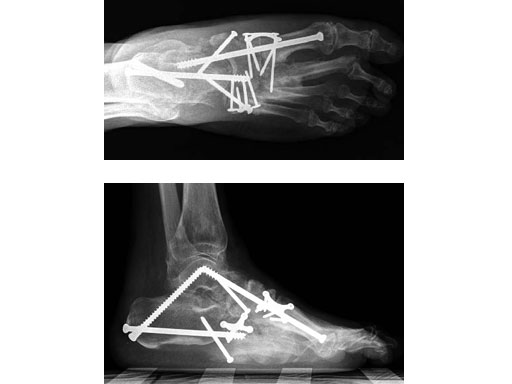

Charcot foot treated with MFB and X-plate

Case 2: 48-year-old male

Case provided by Andrew K Sands, New York, USA

Charcot foot treated with MFB and X-plate.